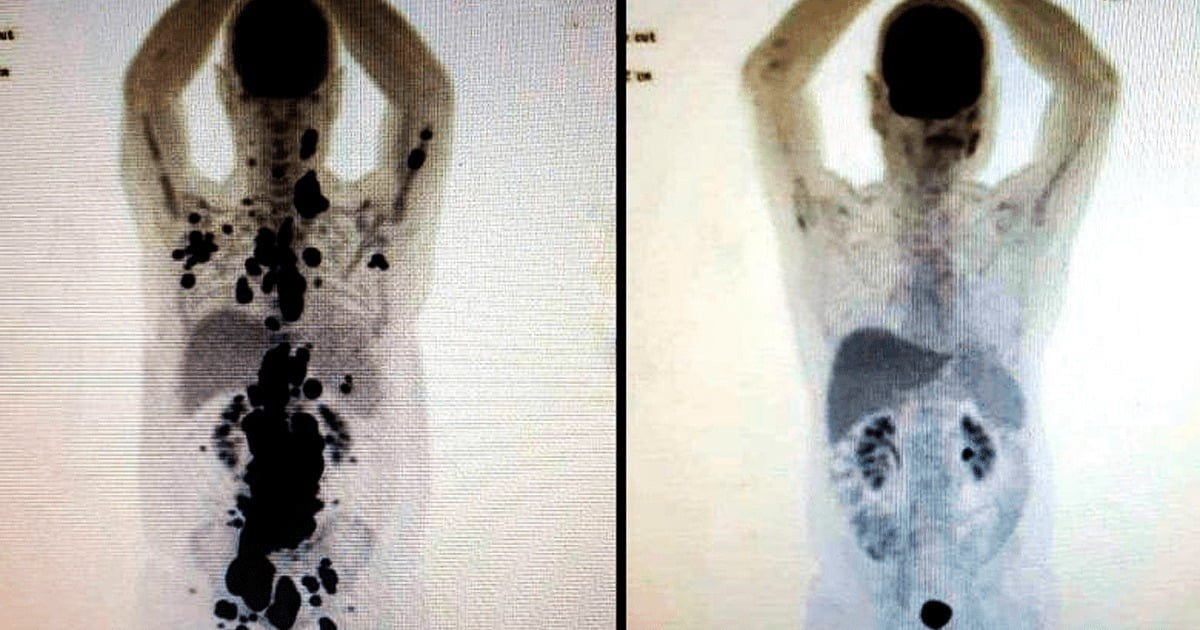

Paulo Peregrino è stato diagnosticato con un cancro alla prostata nel 2010 e, circa dieci anni dopo, ha scoperto di avere un linfoma non Hodgkin, secondo quanto riferito dall’agenzia di stampa A24. Dopo aver esaurito tutte le opzioni di trattamento per il suo linfoma, incluso un trapianto di midollo osseo e 45 sessioni di chemioterapia nel corso di cinque anni, Paulo è stato selezionato per la terapia CAR-T. Sorprendentemente, a seguito del trattamento innovativo, il suo tumore è completamente scomparso.

“Ora dobbiamo monitorare attentamente il caso. Sappiamo che la malattia potrebbe ripresentarsi dopo un certo periodo di tempo. Parliamo solo di una completa guarigione dal cancro dopo cinque anni. Tuttavia, ciò che abbiamo ottenuto è molto incoraggiante, poiché non c’erano più altre opzioni terapeutiche per lui”, ha dichiarato il dottor Vanderson Rocha, medico e ricercatore presso la Facoltà di Medicina dell’USP, che ha partecipato al trattamento di Paulo Peregrino. Dei pochi pazienti sottoposti a questa terapia in Brasile, il 60% ha visto scomparire il cancro in soli 30 giorni.